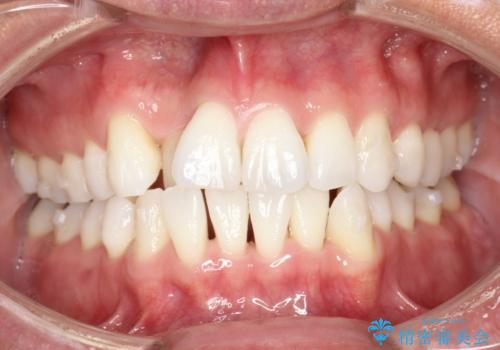

内側に入ってしまった前歯を正しい位置へ インビザライン矯正

右上の前から2番目の歯が引っ込んで、下の前歯にはガタガタがありました。

上下の歯と歯の間を少量ずつ削りスペースを作り、インビザラインにて並べる計画としました。

目立たずに矯正治療を終えることができたことに満足していただけました。